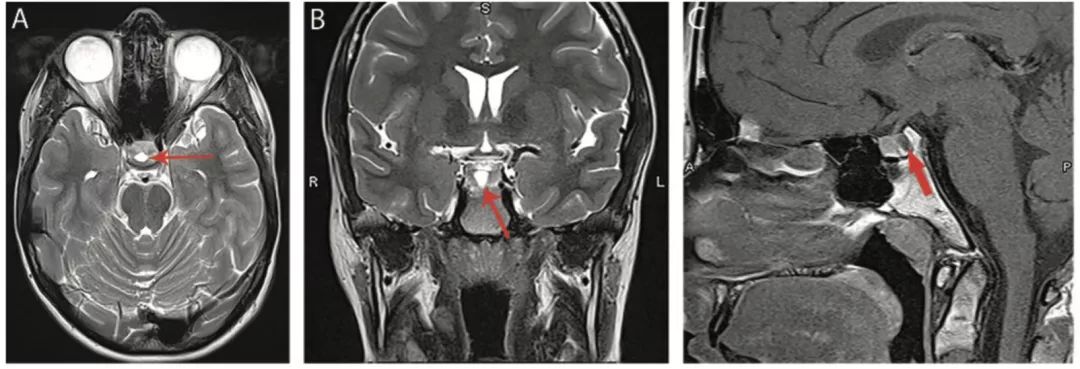

图16 Rathke囊肿

轴位T2WI像(A)、冠状位T2WI像(B)和矢状位T1WI像(C)显示垂体间质部(箭头)附近T2高信号和T1低信号的无增强的囊肿(箭头)。